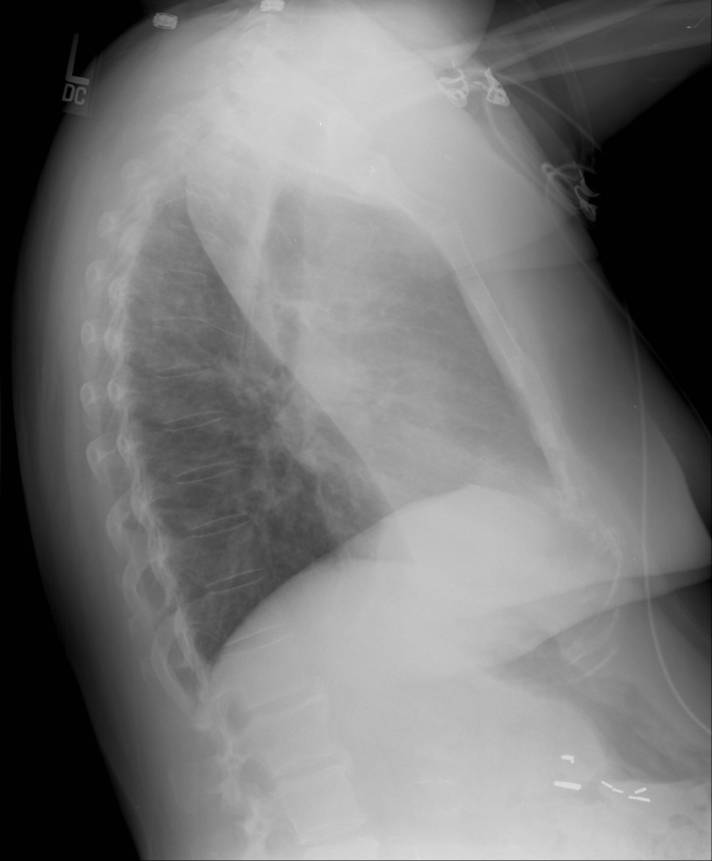

She presented to an outside hospital emergency department and was found to have an abnormal chest x-ray. Posterior-anterior (PA) and lateral films were provided (Figures 1 and 2).

Figure 2. Lateral view on chest x-ray demonstrating left upper lobe consolidation.